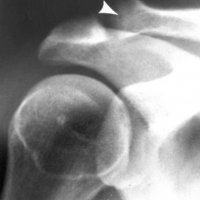

Distal clavicle osteolysis is a unique disease most likely due to an overuse phenomenon. Distal clavicular osteolysis (DCO) follows both chronic repetitive stress and single acromioclavicular trauma. Acute distal clavicular osteolysis was first described in 1936.

The exact aetiopathogenesis is unclear, but AC-joint trauma and subchondral microfractures seem to be involved. Subsequent attempts at repair are insufficient and the final result is osteolysis. It is unclear why changes predominate in the distal clavicle while the acromion is relatively spared.)

Mostly affected males in their 20s and commonly seen in weightlifters, symptoms usually begin with an insidious aching pain in the AC region that is exacerbated by weight training. Clinical findings are often nonspecific and frequently overlap with those of labral or rotator cuff tears. On examination, patients have point tenderness over the affected AC joint and pain with a cross-body adduction maneuver.

Conventional radiographs may remain normal during the first months or years. A 15° cephalad inclination avoids superposition of the scapular spine with the AC-joint (Zanca view).

Radiographic changes include cortical thinning, irregularity and microcysts in distal clavicle and mild AC–joint widening. A late finding is tapering of the distal clavicle.

MRI is far more sensitive to detect DCO in an early stage. The most common MR-finding is bone marrow oedema in the distal clavicle, sometimes also in the articular part of the acromion, but less distinct.

Often, a hypointense line is seen in this area of clavicular bone marrow oedema, representing a subchondral fracture. AC-joint abnormalities are common, and include effusion, mild widening, intra-articular bone fragments and capsule hypertrophy. Other MR-findings are similar to those seen on radiographs, as described above.

Bone scan may also shows increased uptake in the distal clavicle, which could be seen earlier than radiographic changes.

Treatment is essentially conservative, consisting of rest and nonsteroidal anti-inflammatory drugs (NSAID's), and is usually successful. In severe cases, resection of the distal clavicle is indicated. If left untreated, the process may cause progressive resorption of lateral aspect of the clavicle, erosions and cupping of the acromion and dystrophic calcifications.

DCO should be considered in the differential diagnosis of shoulder pain in the appropriate population. Therefore, analysis of MR arthrographic studies of the shoulder should not be restricted to evaluation of the rotator cuff and capsulolabral system, but the AC-joint should be scrutinised as well.